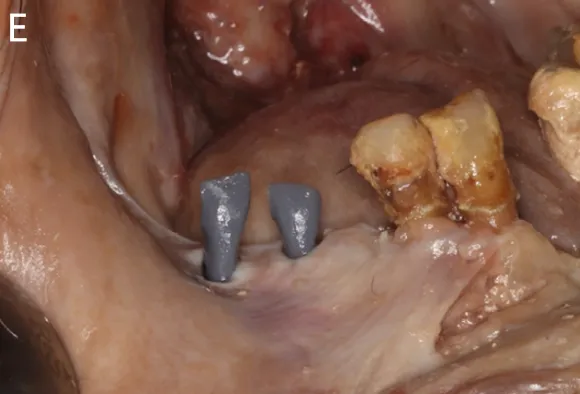

图8:1例右下智齿移植至第一磨牙的临床病例(图引自Tsukiboshi M, Tsukiboshi C, Levin L. A step-by step guide for autotransplantation of teeth. Dent Traumatol. 2023;39 Suppl 1:70-80. doi:10.1111/edt.12819)(A)术前曲面体层片;(B)右下第一磨牙根尖片;(C)右下第一磨牙口内照;(D)右下第一磨牙CBCT矢状位截图;(E)右下第一磨牙远中根CBCT的冠状位截图;(F)右下第一磨牙CBCT轴位截图;(G)3D打印供体牙模型;(H)右下第一磨牙拔除后根尖片;

doi:10.1016/j.joen.2023.06.008)数字化手术导板辅助的自体牙移植:(A)拔除供体牙;(B)数字化手术导板辅助下受牙区牙槽窝预备;(C、D)确认受牙区牙槽窝预备情况;(E)3D打印供体牙模型试戴;(F)将供体牙移植到牙槽窝